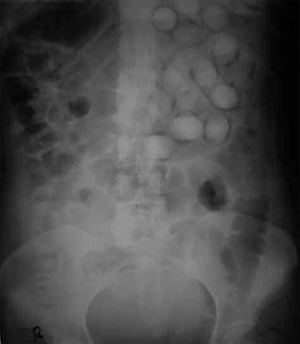

Body packing

- Body packers, also called "mules", swallow or insert drug filled packets into body cavity, usually to smuggle them across borders

- Each packet contains about 10g of drug and body packers ingest between 50 to 100 drug containers at a time[1]

- Imaging: KUB, CT abdomen pelvis